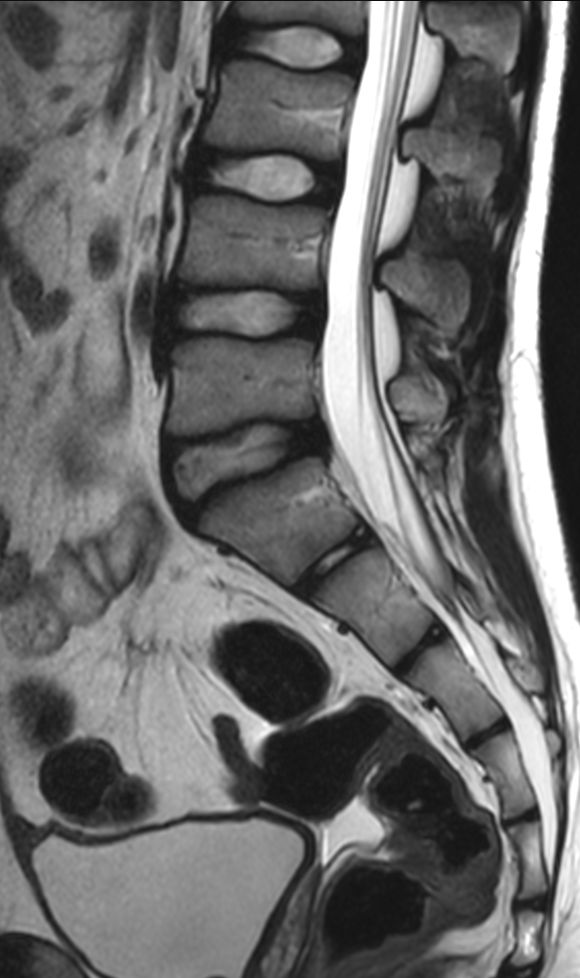

Sagittal T2w TSE (L-Spine)